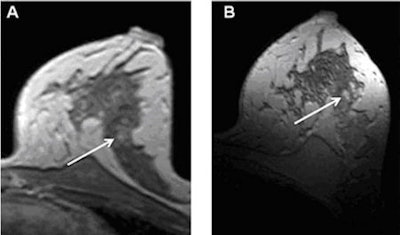

| T1-weighted postcontrast imaging of a 49-year-old woman; suspicious lesion in the lateral side of the breast at 1.5 tesla (A) and more clearly at 7 tesla (B). All images courtesy of Dr. Lale Umutlu. |